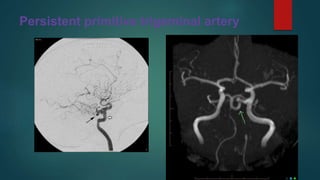

Persistent primitive trigeminal artery

• #3 Digital subtraction angiogram of the internal carotid artery, lateral view, demonstrates a large tortuous vessel (arrow) passing from the internal carotid artery (open arrow) to the basilar artery (arrowhead), and supplying the posterior circulationLarge persistent trigeminal artery passing from the left ICA to the terminal basilar artery via the cavernous sinus.  Note the grossly hypoplastic vertebro-basilar arterial system as a result of this congenital anomaly with most posterior circulation blood coming from the left ICA via the trigeminal artery Persistent primitive trigeminal artery (PPTA) is one of the persistent carotid-vertebrobasilar anastomoses.

• #4 There is direct communication between the basilar artery and left internal carotid artery, in keeping with a persistent left trigeminal artery